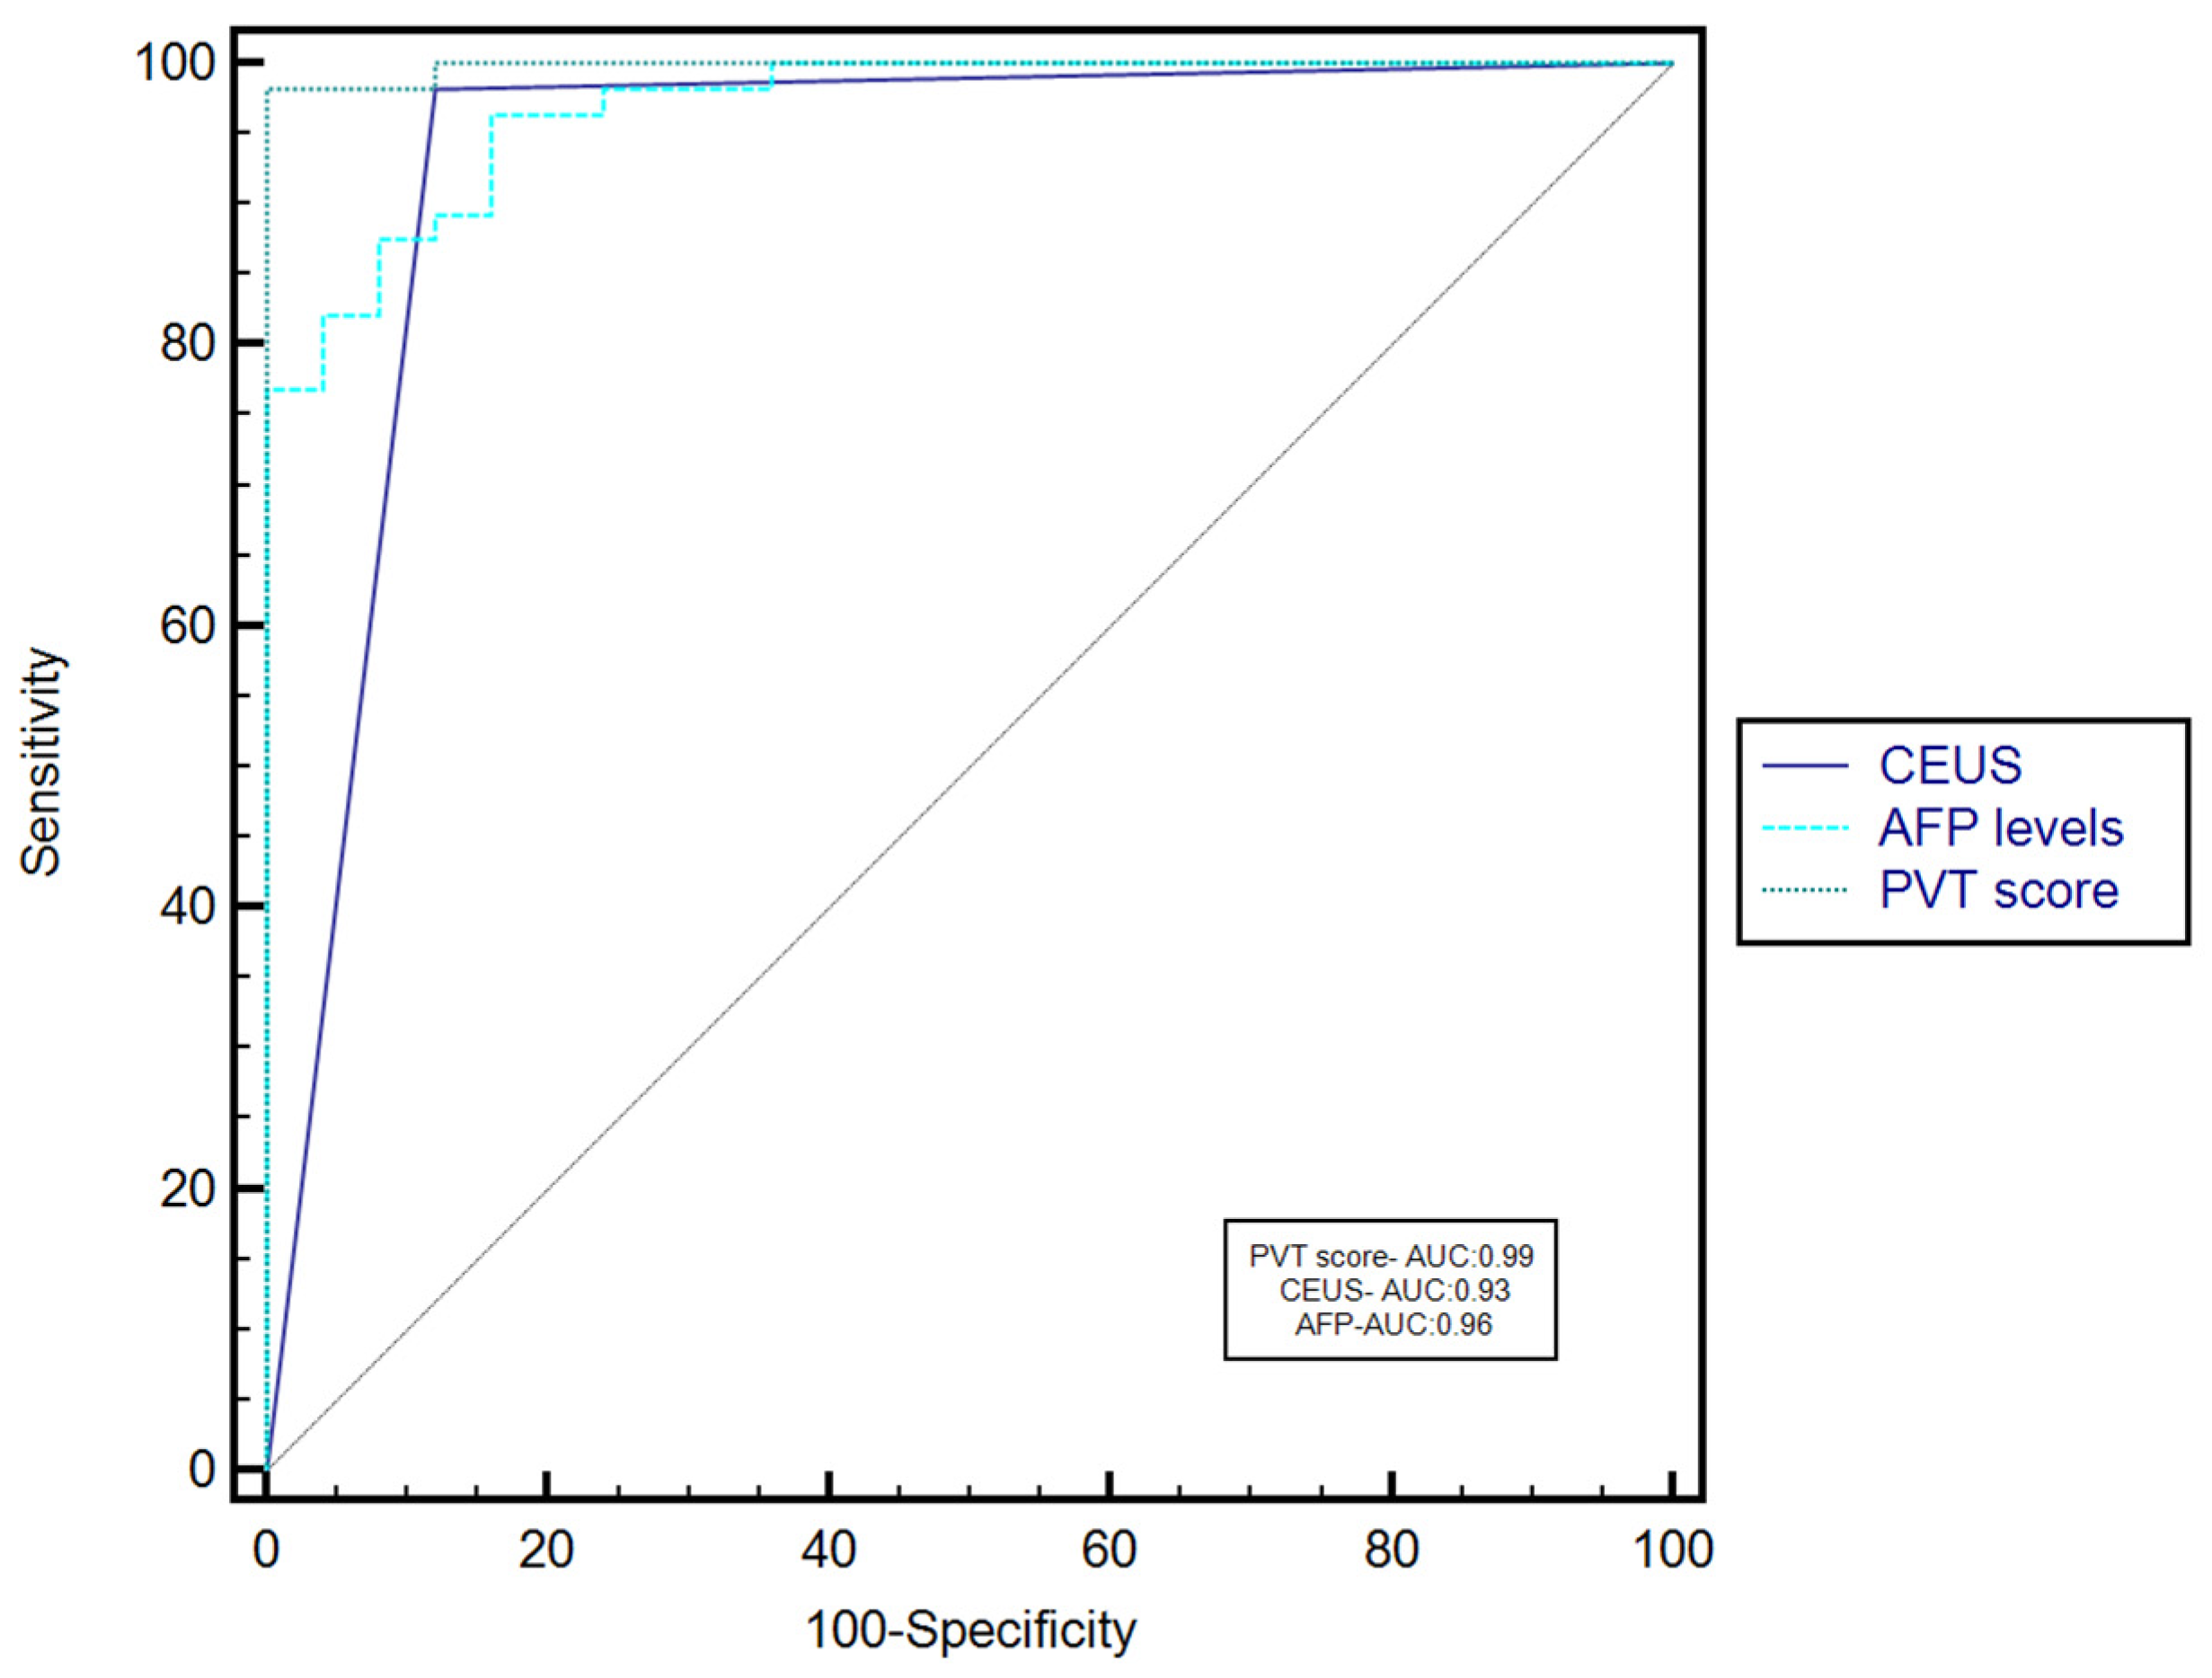

3.5. The Performance of CEUS for the Characterization of PVT

3.6. The Performance of the Combined Use of AFP Serum Levels and CEUS for the Characterization of PVT